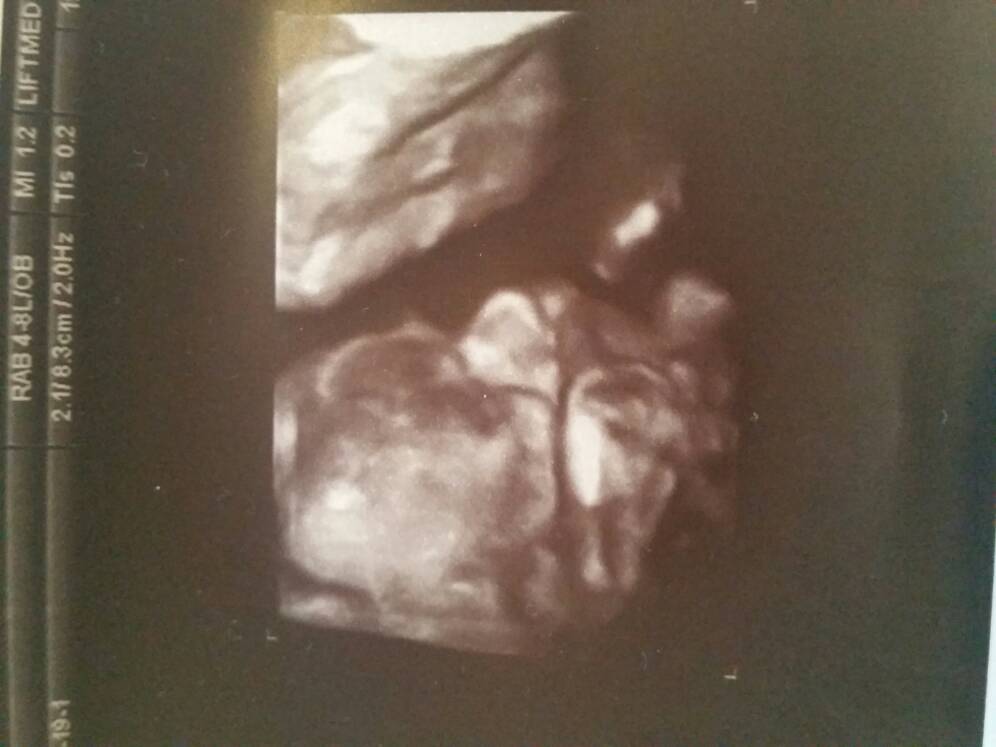

Wrzucam zdjęcia maluszka [emoji4]

Profil, dziurki w nosie i wiadomo co [emoji23]